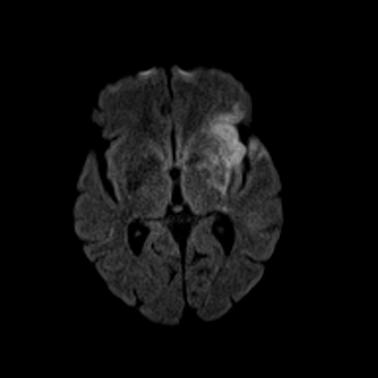

Aufgrund der guten Gewebedifferenzierung verwenden wir die Kernspintomographie (MRT) in der Neuroradiologie zur Untersuchung von Gehirn, Gesicht und Augen sowie von Wirbelsäule und Rückenmark. Schlaganfälle lassen sich postakut minutenschnell lokalisieren und auf ihre Ursache hin untersuchen. Winzige Tumoren, Hirnabbauprozesse, Gefäßmissbildungen, Enzephalitiden (Gehirnentzündungen), Anfallsursachen (Epilepsie) oder Unfallfolgeschäden können gut differenziert werden.

Schlaganfall 1

Schlaganfall 2